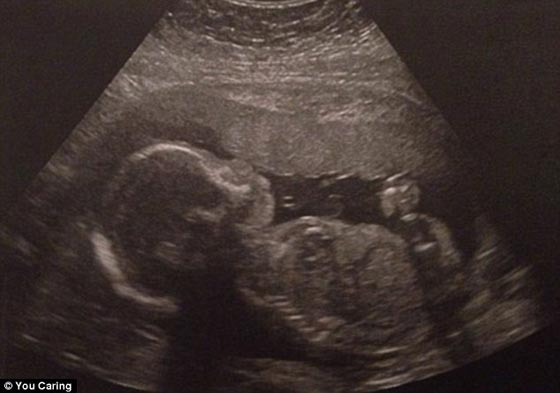

حين كانت روبين بنسون في اسبوعها الـ 22 من الحمل في شهر ديسمبر / كانون الاول، اصيبت بنزف في الدماغ ولم تستعد وعيها فاعلن الاطباء انها ميتة اكلينيكيا. لكن زوجها طلب من الاطباء أبقاءها على قيد الحياة أطول فترة ممكنة لتحسين فرصة الجنين لكي يكبر قليلا ويعيش. ورغم ان روبين كانت في حالة موت دماغي ، فان جسدها كان حيا بفضل اجهزة الاعاشة. وفعلا تمت الولادة القيصرية في نهاية الاسبوع الماضي، حيث ولد الطفل "ايفر كوهين بنسون" في الاسبوع الـ 28 من الحمل وهو بصحة جيدة